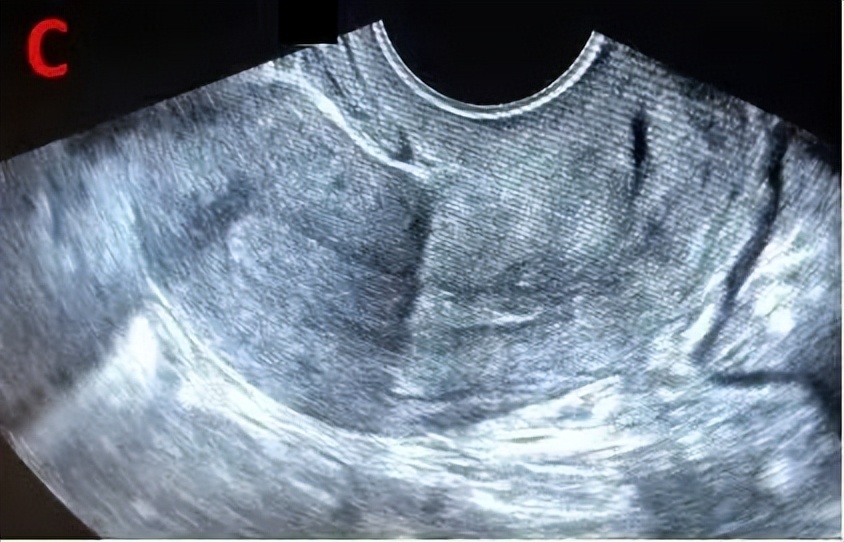

排卵后的变化

成熟卵泡消失或原成熟卵泡直径明显缩小,形态不规则,壁皱缩,卵泡内透声差,可见细弱光点,部分女性会出现子宫直肠凹积液,子宫内膜逐渐由A型转变为C型。